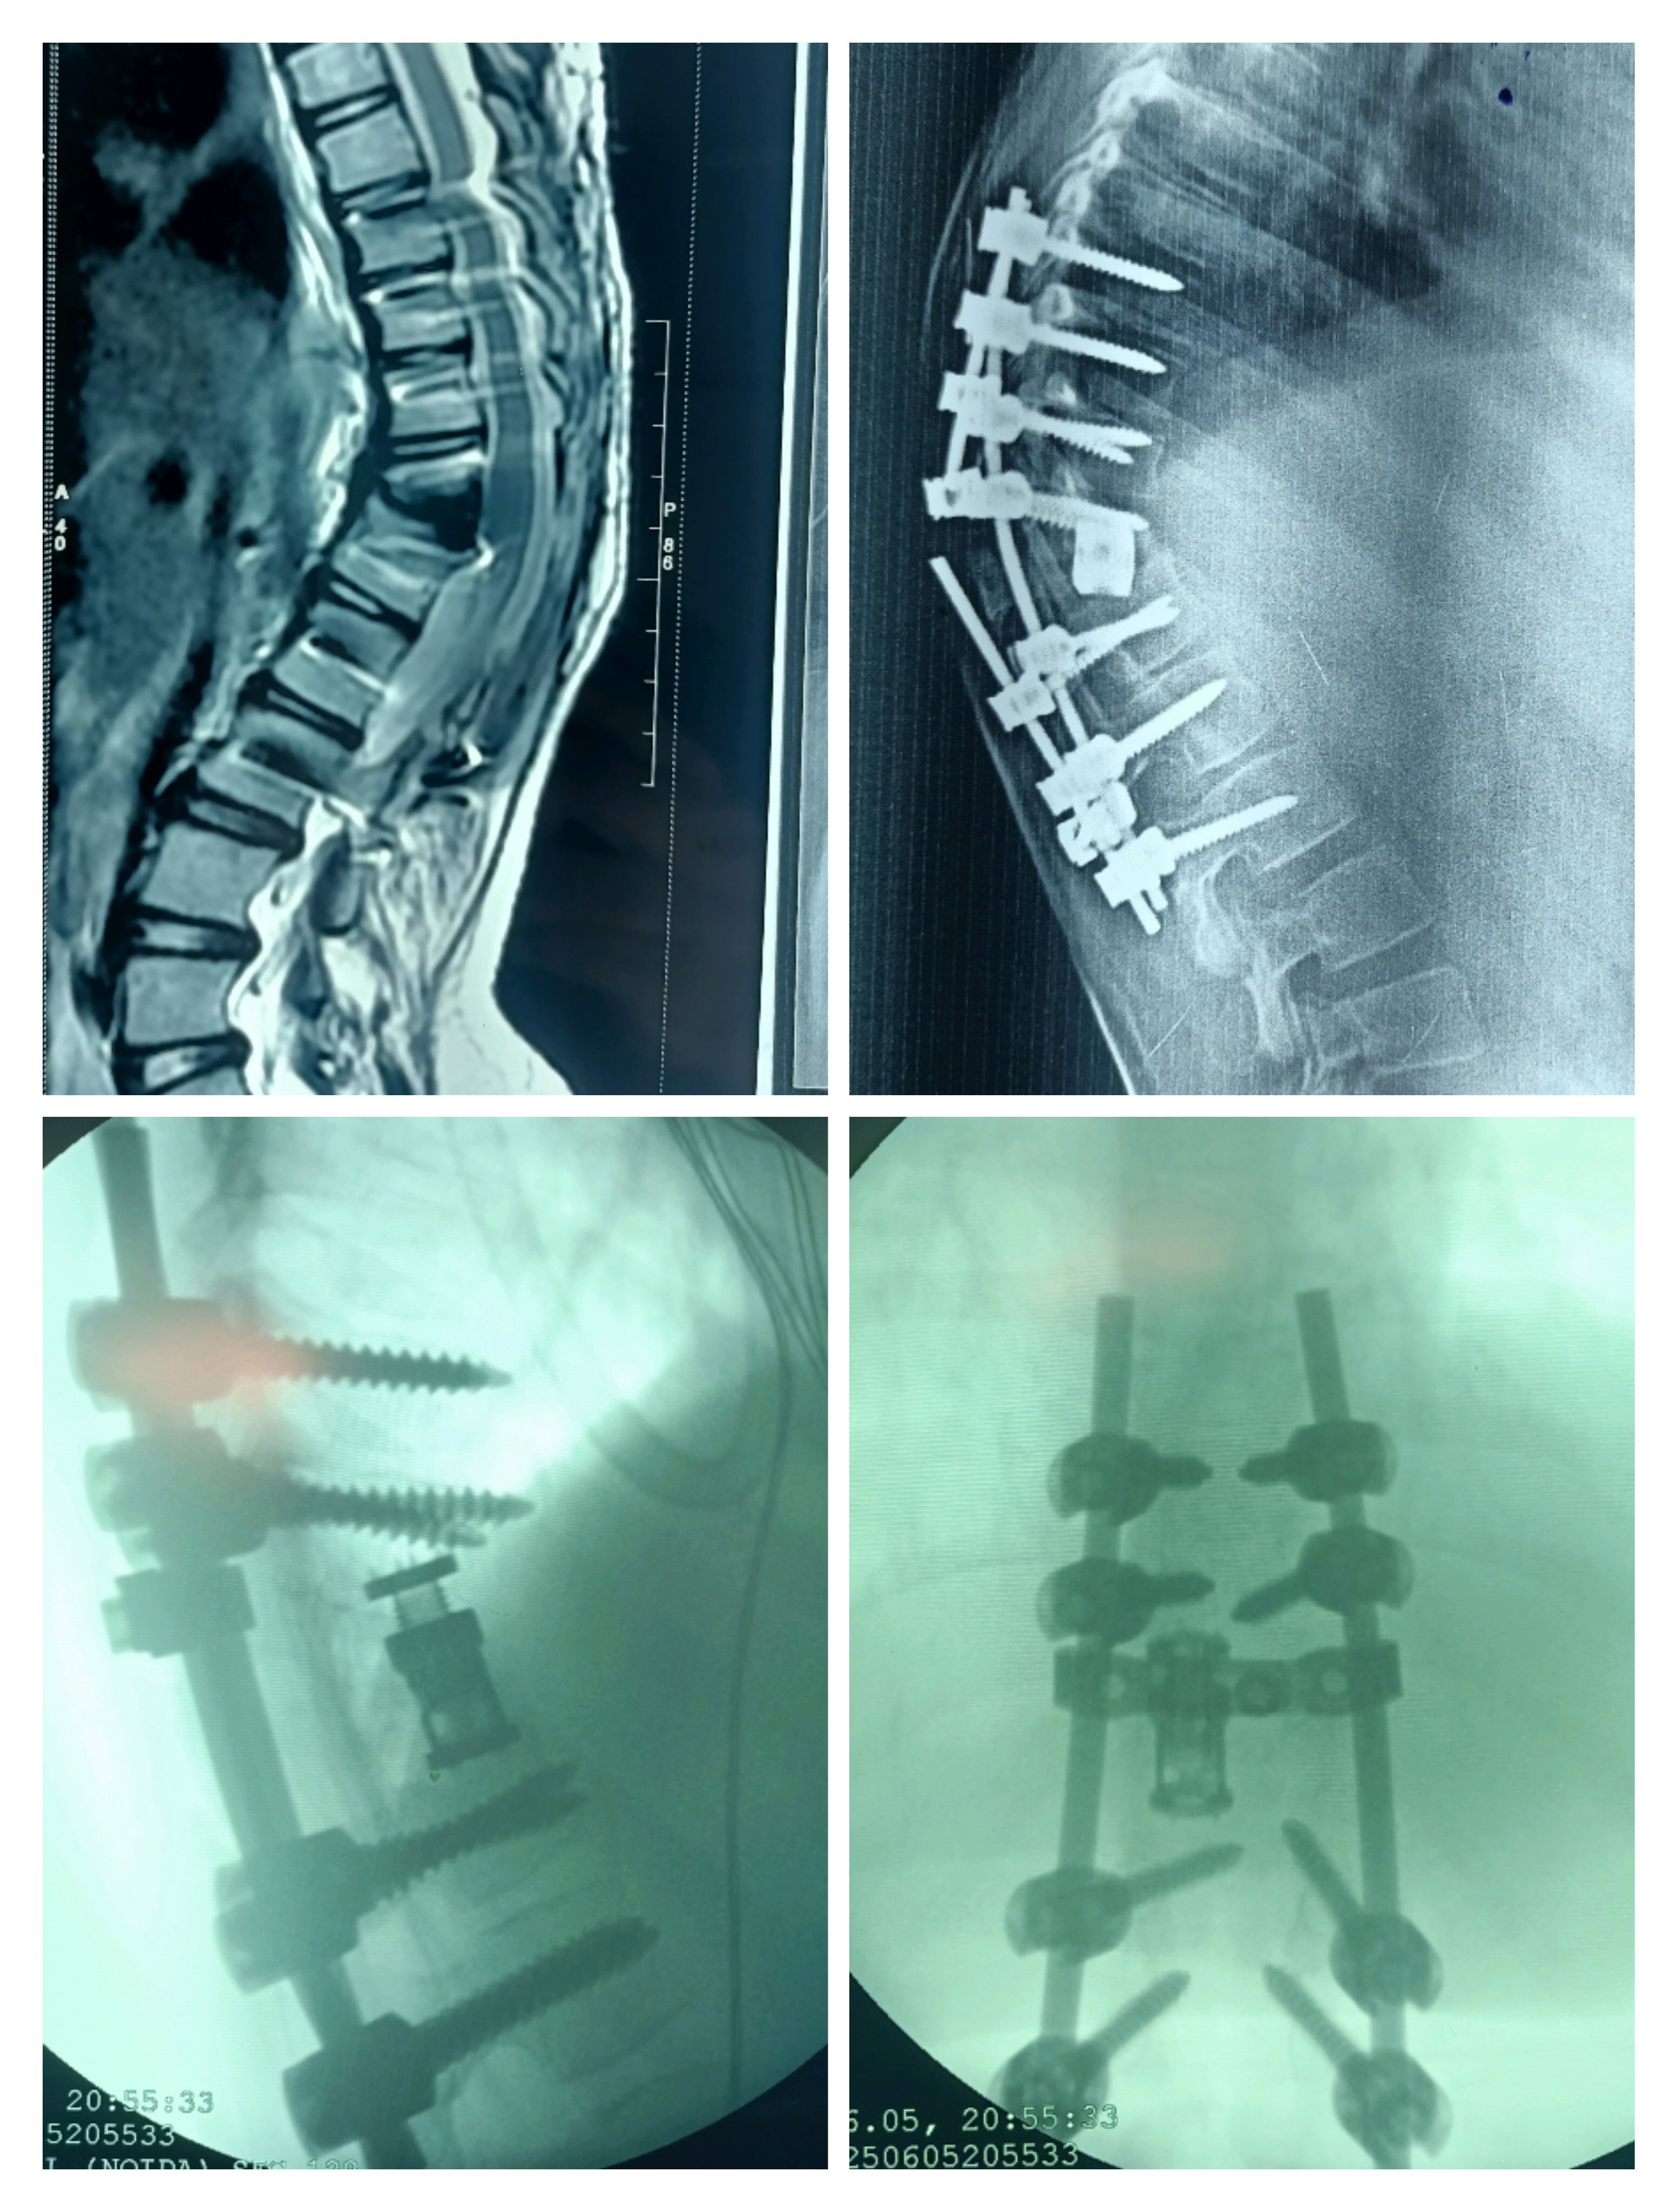

Revision Spine surgery- Post Tubercumar kyphosis T...